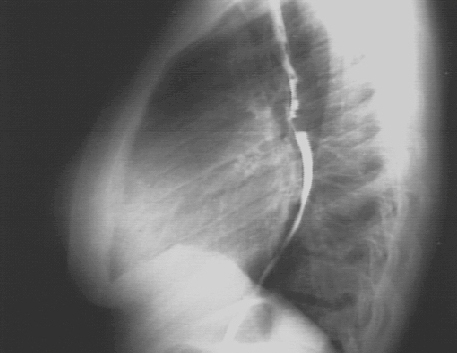

Left Ventricular Enlargement + Left Atrial Enlargement PA and Lat

These chest X rays show left ventricular enlargement and left atrial enlargement.

The lateral view with barium swallow, demonstrates posterior displacement of the esophagus by the markedly enlarged left atrium.